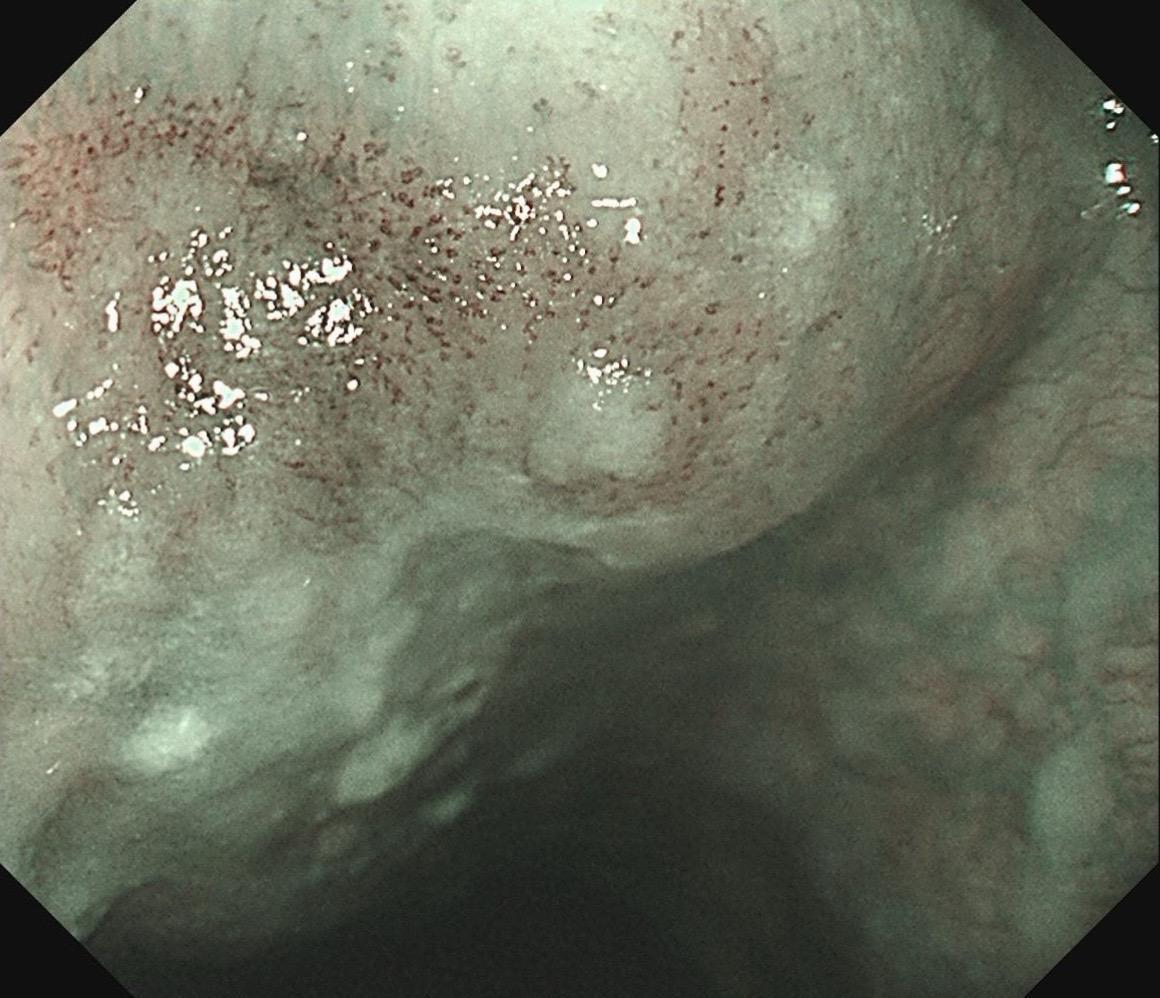

女,73岁,食管双发病变。泰州人,入院系统体检,首次胃镜检查,上段16-19cm见长条状病变,肛侧碘染局部不染;25cm处见一2mm粗糙潮红黏膜,浅凹陷,放大疑似R型不规则血管,卷发样改变,淡染,均行ESD切除。